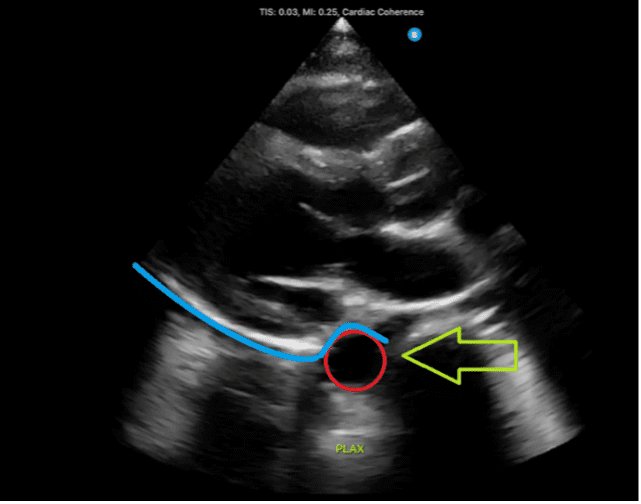

Figure 2: Normal parasternal long-axis view demonstrating the descending aorta, indicated by the red circle and green arrow. A fluid collection located above the aorta, denoted by the blue line, would suggest the presence of a pericardial effusion.